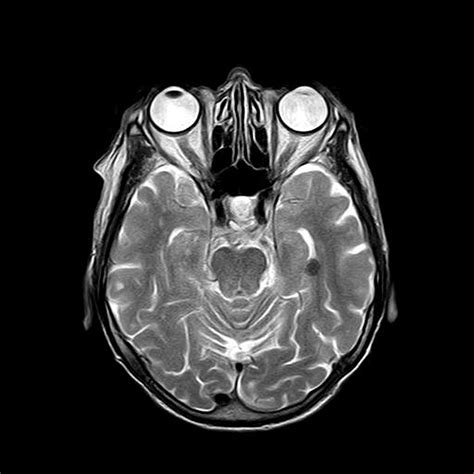

When a physician recommends a brain MRI with contrast, it is often because they need a more detailed look at the structures within your head than a standard MRI can provide. While a regular magnetic resonance imaging (MRI) scan uses powerful magnets and radio waves to create images of the brain's anatomy, the addition of a contrast agent—a special dye—significantly enhances the visibility of certain tissues and abnormalities. This diagnostic procedure is a cornerstone of modern neurology and neurosurgery, helping clinicians diagnose conditions ranging from tumors and infections to inflammatory processes and vascular issues with pinpoint accuracy.

By highlighting these specific areas, the contrast agent allows radiologists to distinguish healthy tissue from diseased tissue. It acts like a spotlight, making lesions, tumors, or areas of inflammation "light up" on the resulting images. Without this enhancement, subtle abnormalities might remain hidden, leading to potentially delayed or incorrect diagnoses.

• mri brain with contrast images